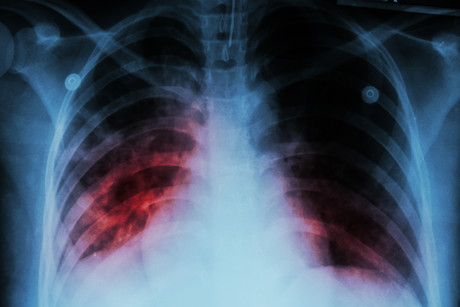

Dr King and his colleagues also wanted to better understand the gut–lung axis — a bidirectional communication system between microorganisms residing in the gastrointestinal tract and the lungs — in order to see how this might be involved in Mtb infection and immunity. To do so, they evaluated a number of lung cell types known to be important for resistance to Mtb infection. Following anti-TB treatment, alveolar macrophages — a type of immune cell located in the airways of mice and humans and the first cell to encounter Mtb upon infection — were compromised in their ability to kill Mtb.